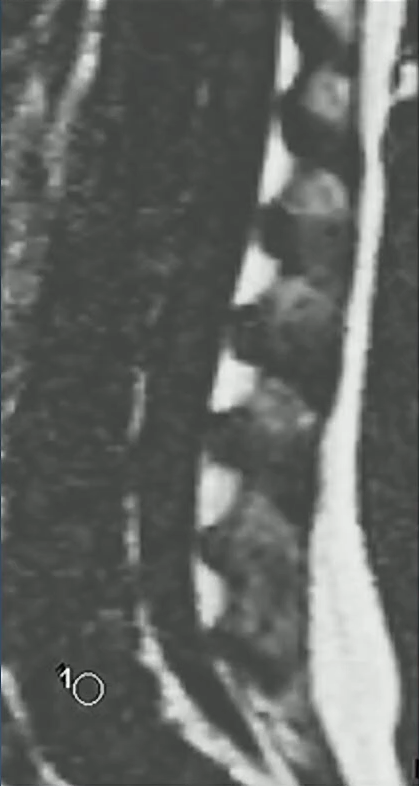

When a pediatric patient presents with back pain, MRI of the spine is a powerful tool to distinguish between benign and malignant processes. In this case of a 7-year-old girl from a Quick Byte presentation by Laura M. Fayad, MD, the imaging reveals systemic replacement of the normal bone marrow.

- Darkness: On T1-weighted imaging, the marrow signal is abnormally dark.

- Vertebral Compression: Multiple areas of the spine show vertebral body height loss and fractures.

- Diagnostic Worry: Indeed, this combination of diffuse signal abnormality and pathologic fractures is highly concerning for leukemia.

- The Dropout Test: In this patient, while fat is clearly visible in the subcutaneous and epidural spaces, there is a complete absence of fat signal within the bone marrow.

- Conclusion: The total lack of marrow fat indicates that the space has been entirely replaced by malignant cells.